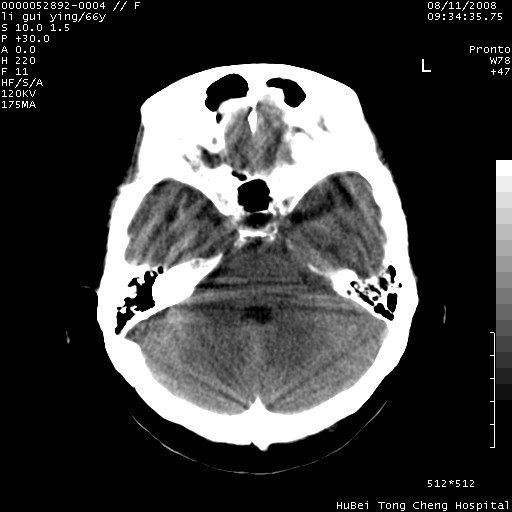

以下是引用yangyudong333在2008-8-12 12:22:00的发言:[br]1.病灶呈圆形[br]2.周围无水肿带[br]3.密度不均匀,内有点状钙化[br]4.无占位效应[br] 考虑良性占位性病变,血管瘤可能性大